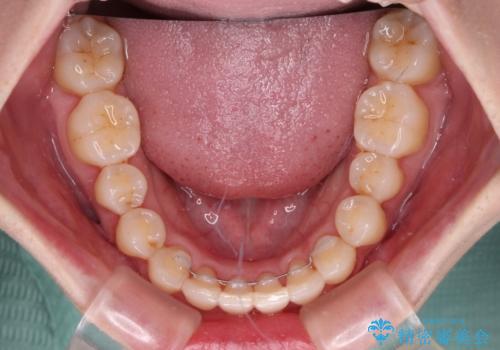

骨格的に下顎が右側に変位していたため、上下正中を合わせることは困難であることは分かっていました。それでも、なるべく合わせるようにとしたため、治療期間は長期間となりました。

長期間とはなりましたが、咬み合わせが改善され、患者様には大変満足していただきました。